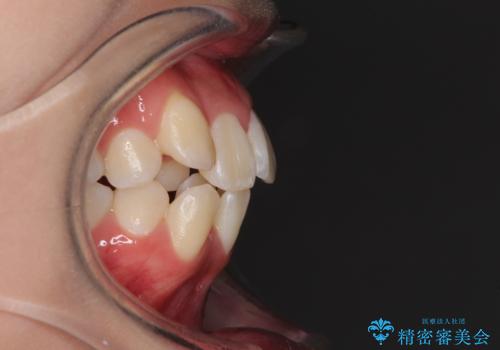

- 八重歯を気にして来院された患者様です。

上下ともに前突感と叢生が認められ、上顎の正中が著しく右側にずれていたため、上下左右第一小臼歯4本を抜歯し、ワイヤー矯正にて治療を行うこととしました。